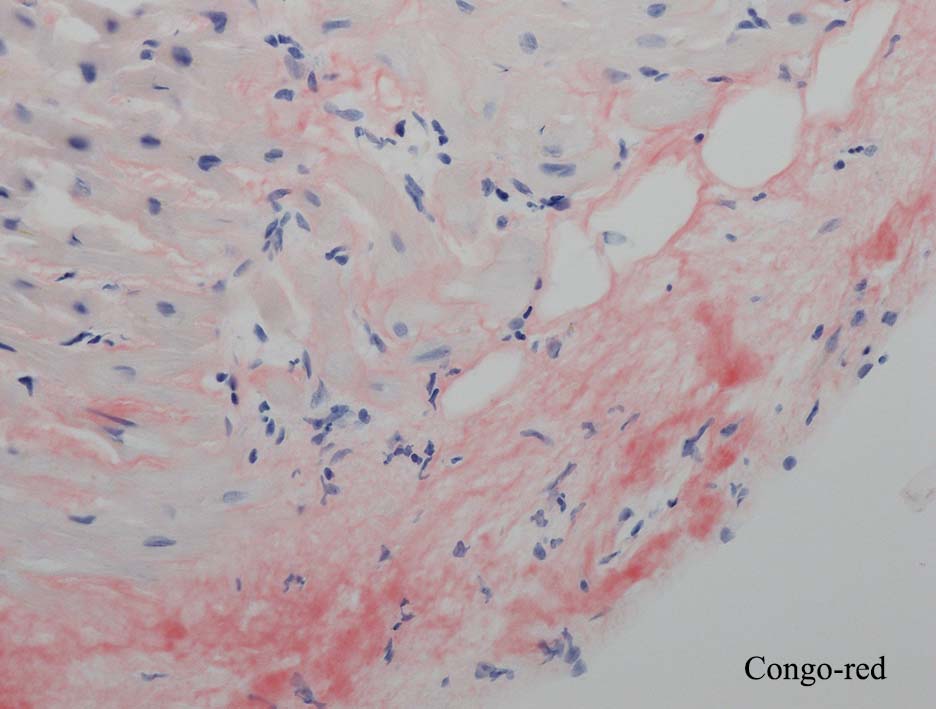

HE所見では, 明瞭な沈着物はわかりにくい. 血管壁が確認できる血管も少ない. congo-red染色で沈着が考えられる所見があり, 簡易偏光で(みずらいけれど)apple-greenの偏光があるように見える.(サムネイルのクリックで大きな画像が見られます)